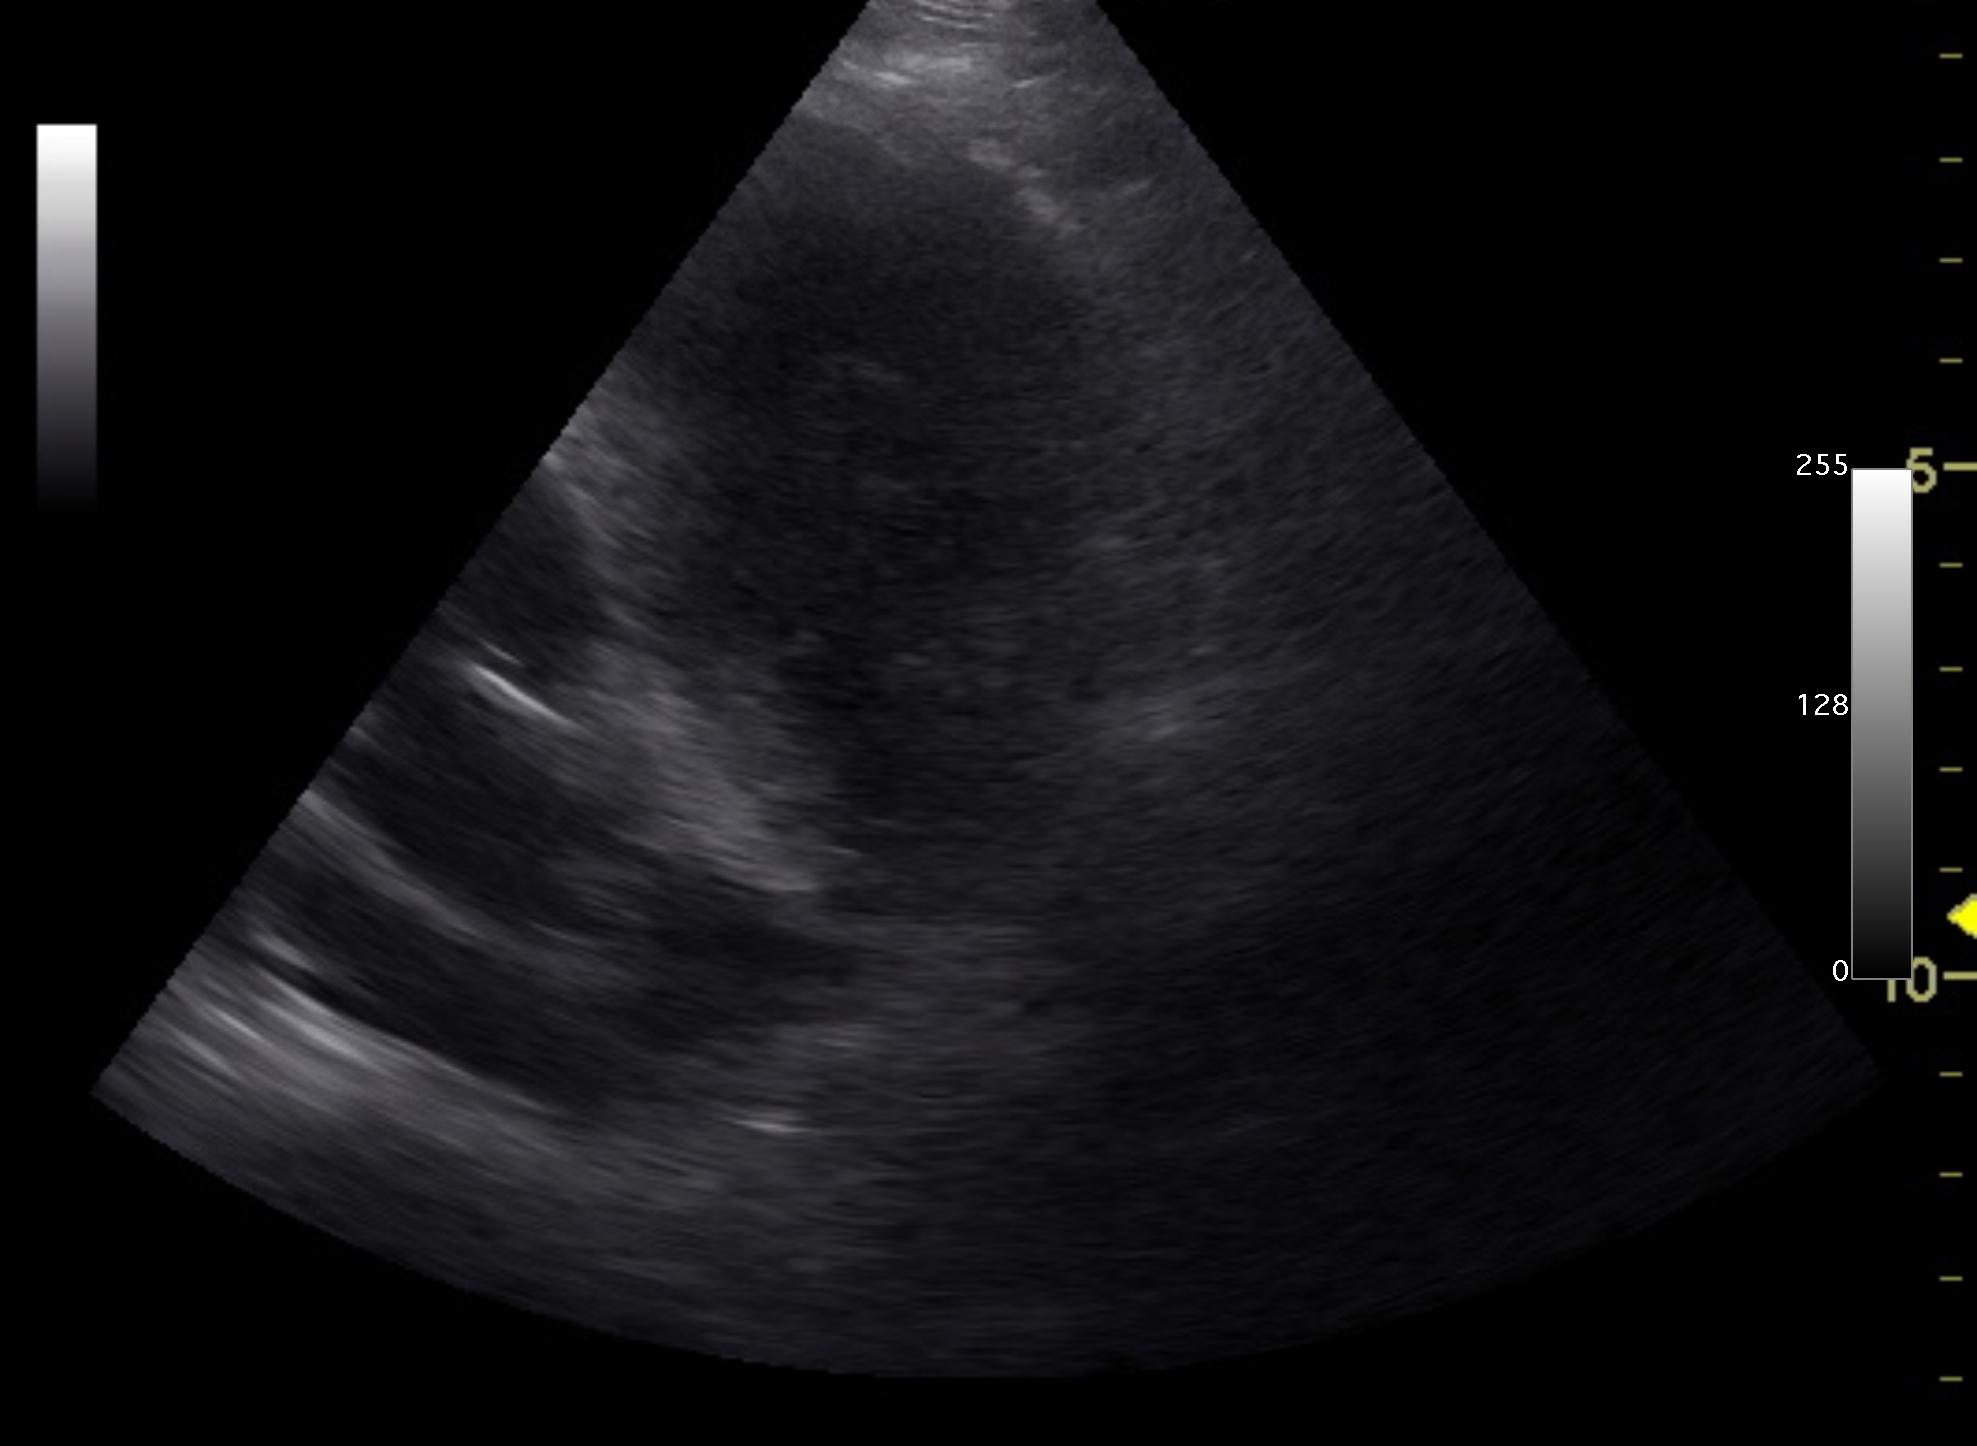

A 9-year-old SF Golden retriever was presented for evaluation of coughing and lethargy. On survey radiographs a left cranial lung mass was evident.

Left cranial lung mass was noted which was significantly hypoechoic and irregular with some cavitation. FNAs were performed without complication. Peripheral air entrapment was noted, which is indicative of lung origin. This may be resectable. CT evaluation would be ideal.